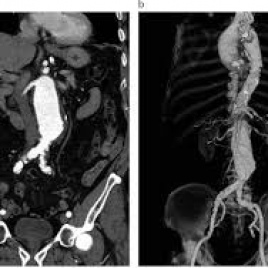

Angiotomografia con protocolo TAVI. Idime. (2024)

IDIME. Instituto de Diagnóstico Médico. Código de Convenio : 8915

BOGOTÁ

Sede Lago:Dirección: Calle 76 No. 13 – 46 / 22

Sede Norte: Autopista Norte No. 122 – 68

Sede Sur: Cra. 21 No. 22 – 68 Sur

BUCARAMANGA

Carrera 27 No. 30 - 15 Segundo Piso Hospital Universitario Los Comuneros

INCLUYE MEDIO DE CONTRASTE